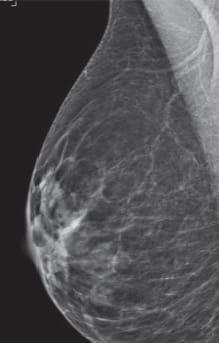

Breast Density Extremely Dense

Category D: Extremely dense